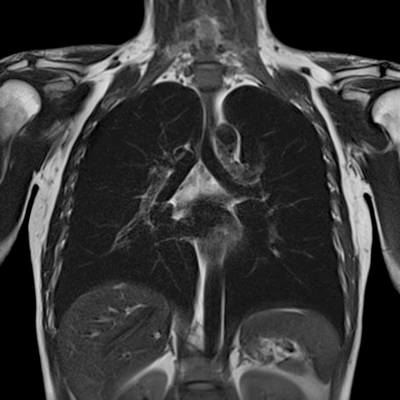

Затемнение в легких на МРТ

МРТ грудной клетки (фронтальная проекция)

Многих пациентов интересует вопрос, что такое затемнение легких, и видно ли патологию на МРТ.

Магнитно-резонансную томографию не часто используют для диагностики органов дыхания. Легочная ткань состоит из заполненных воздухом альвеол, которые визуализируются на снимках размыто. Дыхательные движения и пульсация сердца создают множество артефактов, снижающих качество МР-изображений. При подозрении на воспалительные процессы выполняют, в первую очередь, рентген и КТ легких. Метод магнитно-резонансной диагностики используют для обследования: